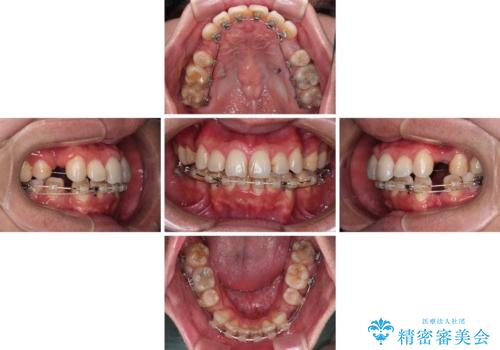

裏側装置での交叉咬合改善は非常に困難なもので、頻繁に装置の脱落がありました。

それでも想定以上に治療期間は長期化せず、咬み合わせも口元も満足のいく仕上がりとなりました。